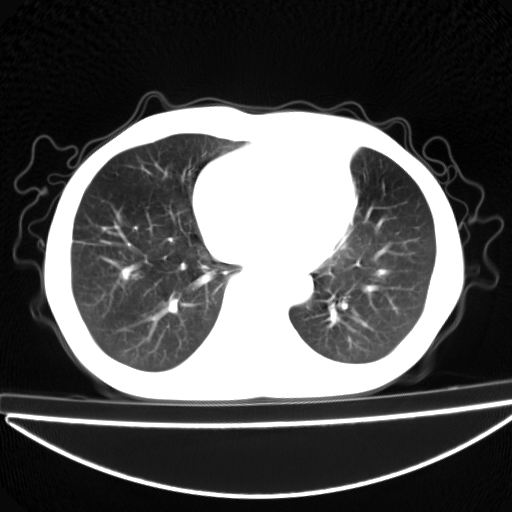

以下是引用杀毒软件在2009-4-28 17:58:00的发言:[br]考虑----左肺慢性肺脓肿形成继发上叶含气不良---抗炎后复查---待排肿瘤所致[br][br][本贴已被 杀毒软件 于 2009-4-28 18:01:26 修改过]